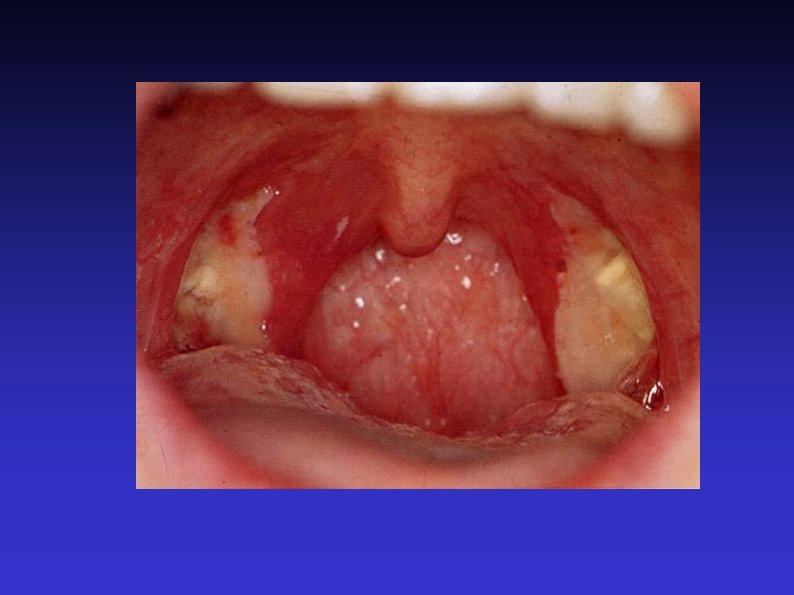

Examination of the throat 4) Oral examination Lips, perioral lesions 1 or 2 tongue depressors (or finger) Inspect tongue, buccal mucosa and oropharynx Salivary duct orifaces Say ‘Ahhh’ Finger examination of tongue, floor of mouth, cheeks and back of throat